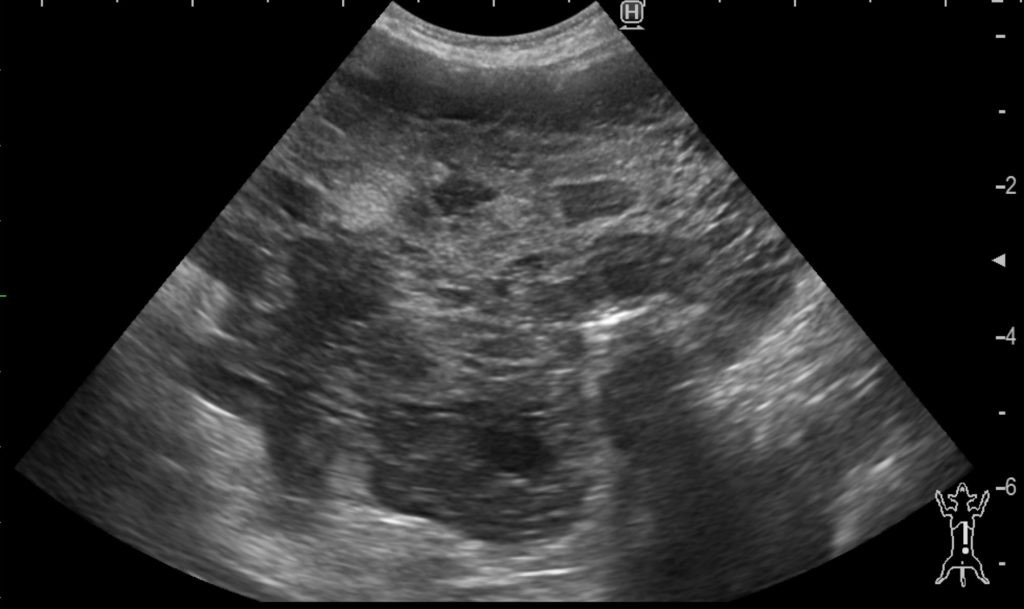

超音波検査

肝臓、胃に接触する形で腫瘤状構造を確認しました。

実際の超音波画像です。充実性ではありますが不均一な不透過性を示していました。